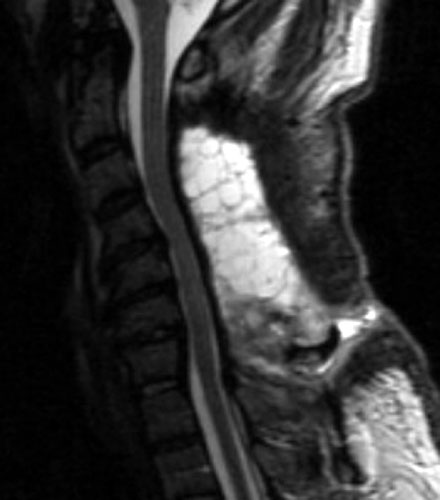

Seroma and Epidural Scar

A B